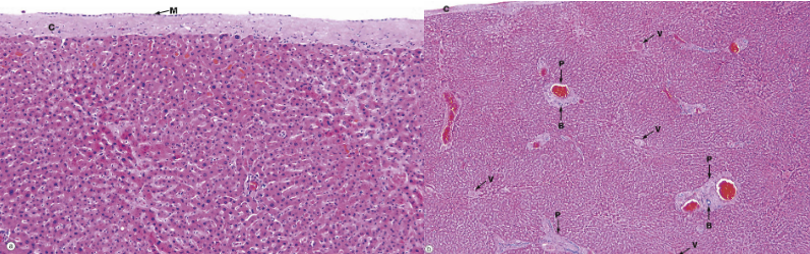

what is the liver stroma? what does it surround? what do these structures contain?

CT cont. w/ fibrous capsule of Glisson

portal space/area → portal triad

contains: BV, nerves, lymphatics vessels (thoracic duct), bile ducts

what are interlobular vessels? septa?

branches of portal v. + hepatic a. occupying portal space

septa → thin CT, divides lobules (contain portal triads)

what is the liver parenchyma composed of?

hepatic cords → organized plates of hepatocytes separated by sinusoidal c.

hepatocytes → large, polygonal cells w/ large # ribosomes, mitochondria, golgi complex, lysosome, peroxisome

what are sinusoidal capillaries (sinusoids)? venous drainage path?

vascular channels btwn hepatic cords

interlobular vessel → sinusoids → central v. → sub lobular v. → IVC

central v. runs through center

where are the perisinusoidal spaces (space of Disse)? function?

btwn sinusoidal endothelium (hepatic a. + portal v.) + hepatocytes (bile duct + outer)

XC of materials here → hepatocytes have microvilli extending to perisinusoidal space to absorb

what are the cells of the perisinusoidal spaces (space of Disse)?

kupffer cells (endothelium) → MO

Ito cells (microvilli) → store fat + vit A

activated via cytokines → fibrosis

what are the liver lobules (functional units)?

hepatic lobule → anatomical, site of lymph formation

portal lobule → bile sec. (exocrine), contain bile duct

liver acinus → correlation btwn blood perfusion, metabolic activity, liver pathology